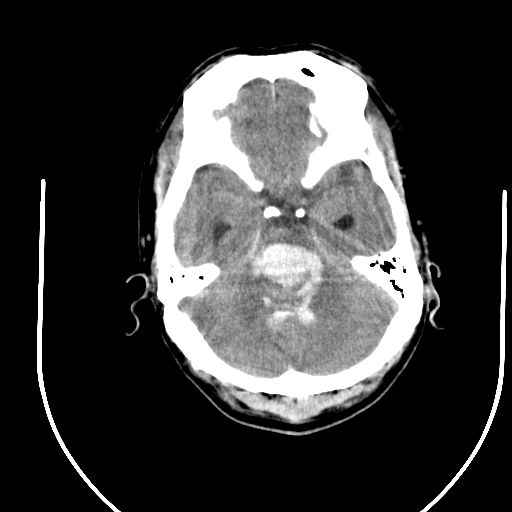

标题: CT24997:M,60Y,突发昏迷30分钟,有高血压病史。 [打印本页]

标题: CT24997:M,60Y,突发昏迷30分钟,有高血压病史。

右侧基底节区脑出血并破溃入脑室。

1右侧基底节脑出血伴脑干出血并破入脑室系统脑疝形成2梗阻性脑积水

1)右侧基底节脑出血伴脑干出血并破入脑室系统。2)大脑镰下疝。3)梗阻性脑积水。